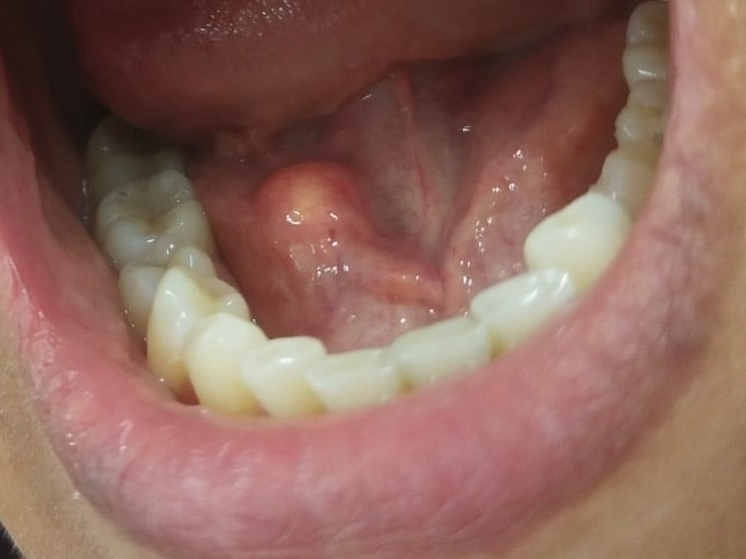

В рамках этого проекта 48-летняя жительница Чебоксар обратилась с жалобами на припухлость под нижней челюстью и боль, возникавшую во время еды.

Осмотр провела заведующий отделением терапевтической стоматологии Оксана Новошинова. Специалист выявила увеличение поднижнечелюстной слюнной железы и уплотнение в области её выводного протока. Пациентку в срочном порядке направили к стоматологу-хирургу Ранилу Камальдинову. Врач поставил диагноз: закупорка протока слюнной железы камнем.

Образовавшийся конкремент был успешно удалён в день обращения женщины за помощью. Благодаря оперативному вмешательству функция слюнной железы полностью восстановилась, что позволило пациентке вернуться к нормальной жизни.